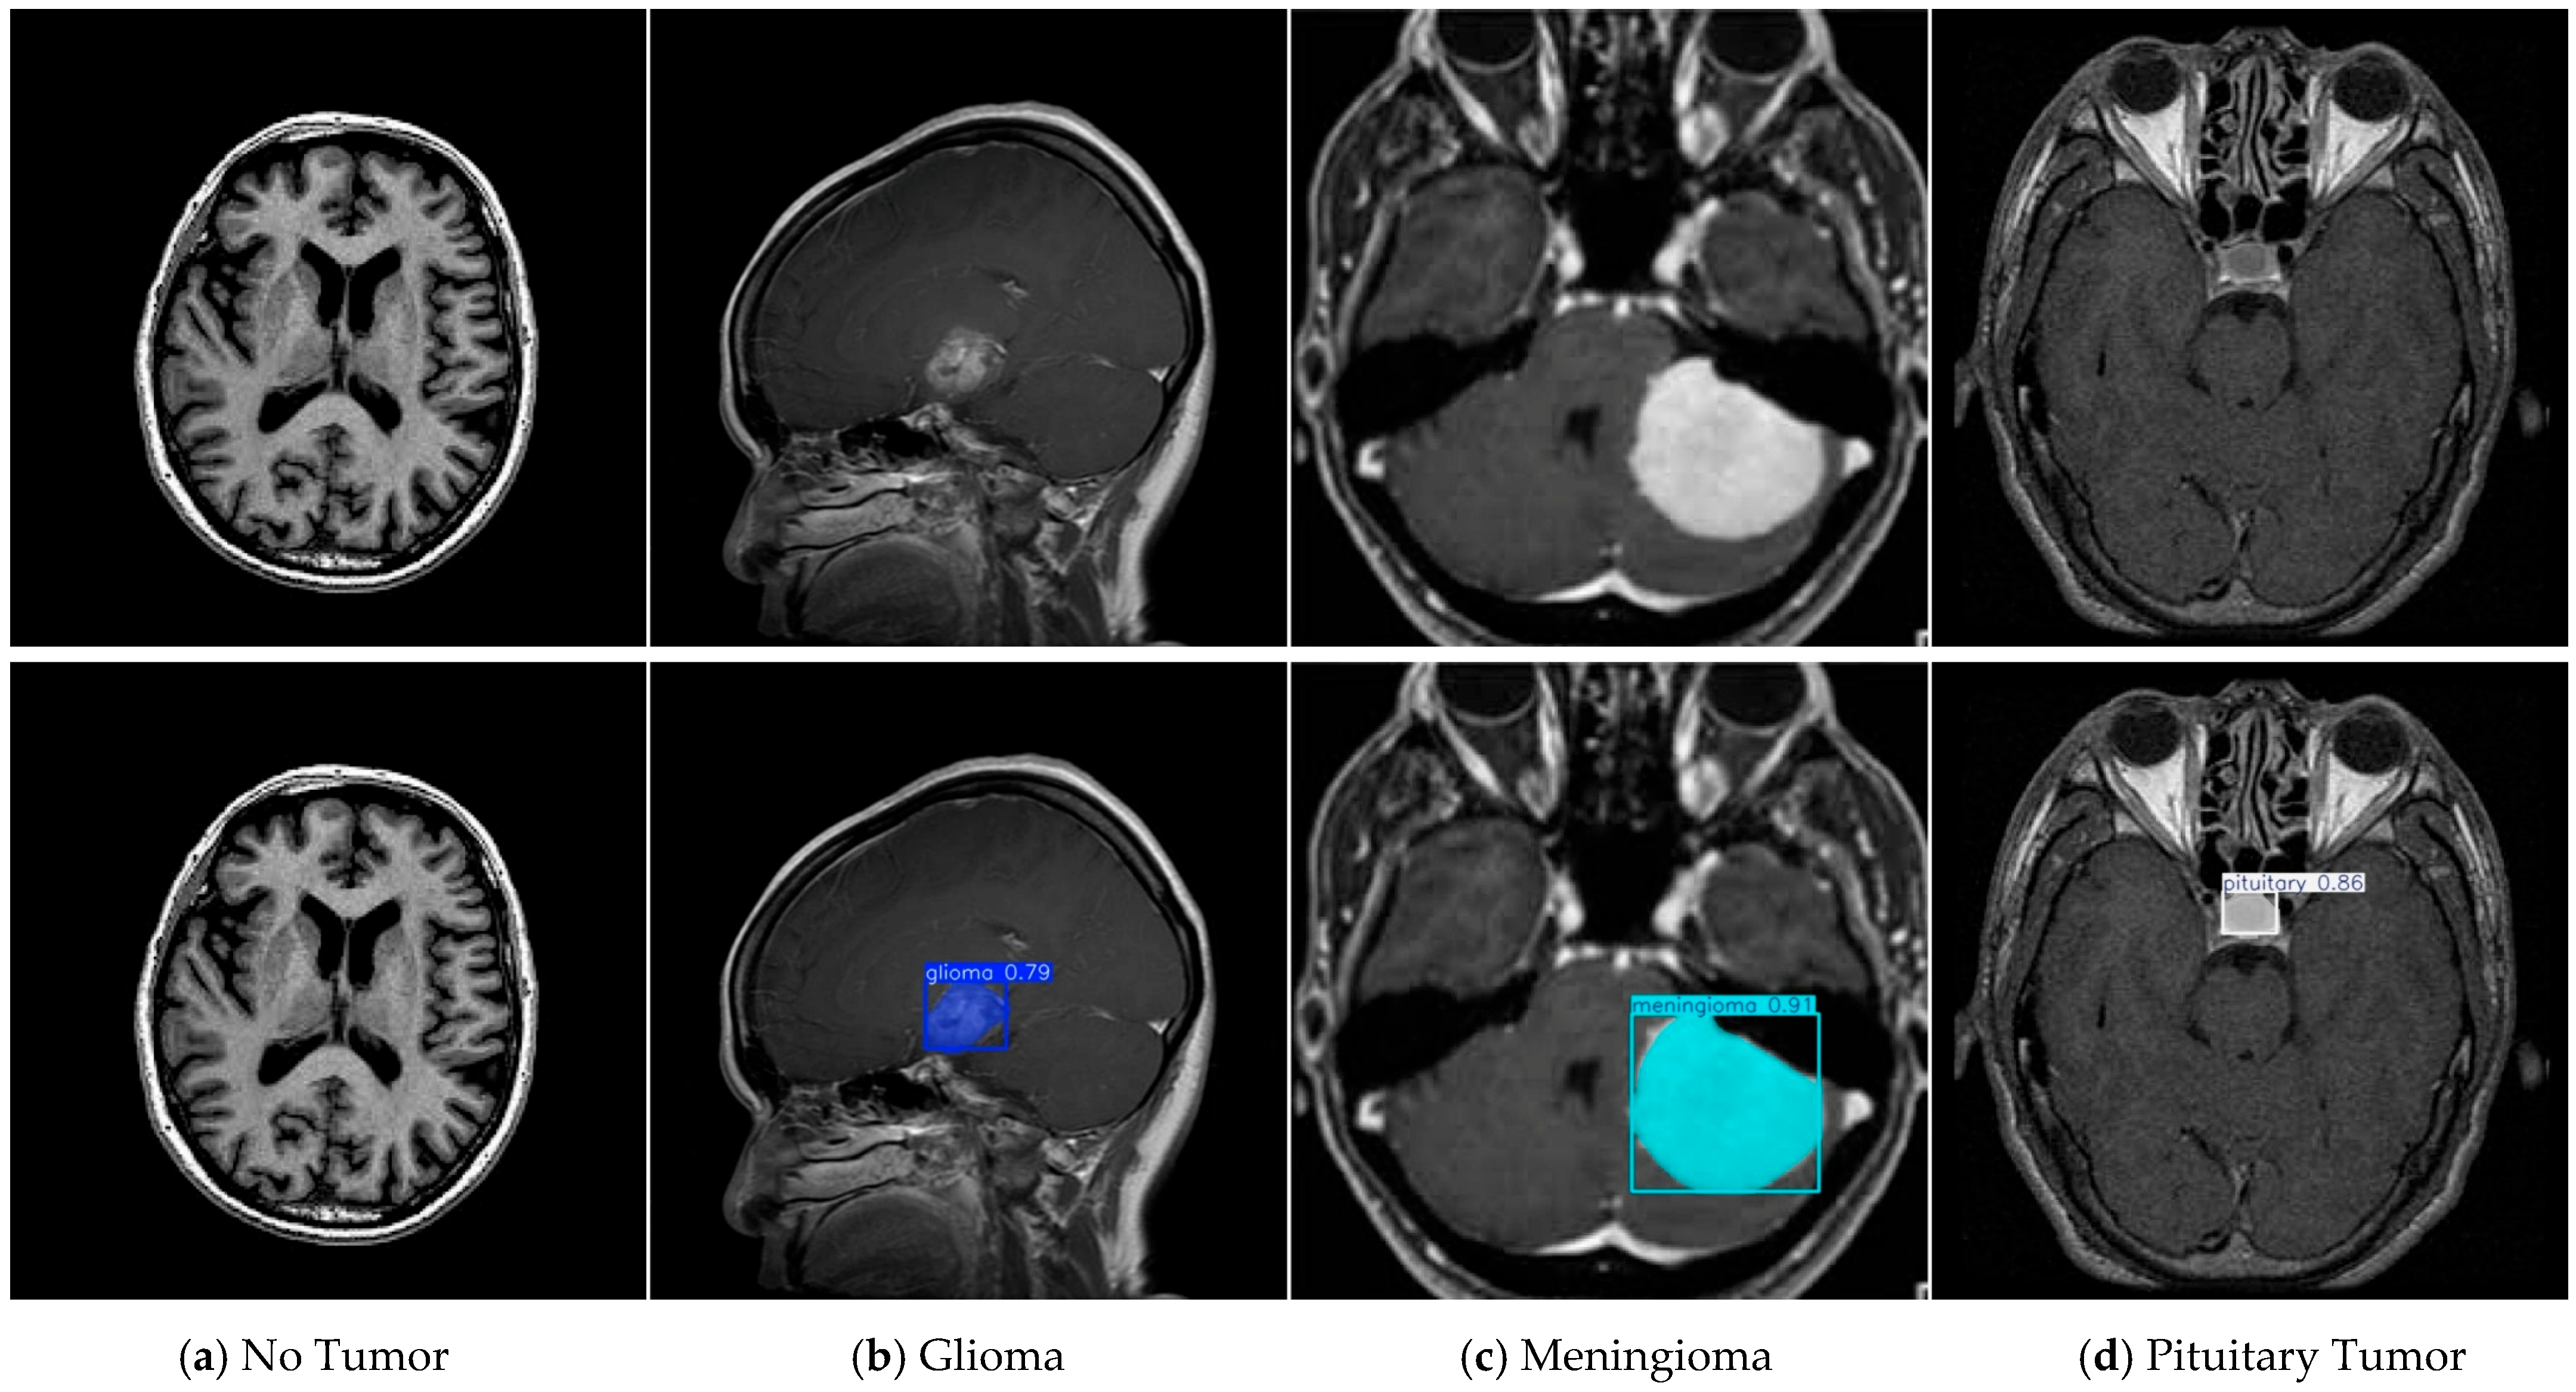

4.1. Dataset

4.8. Discussion on Brain Tumor Classification Ability